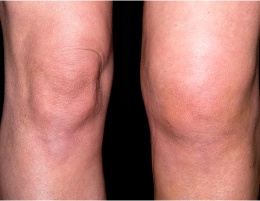

무릎이 붓고,

관절 잠김

관절염 + 휜다리 동반

휜다리교정술 (절골술)

무게 중심을 바꿔 관절염 진행 지연